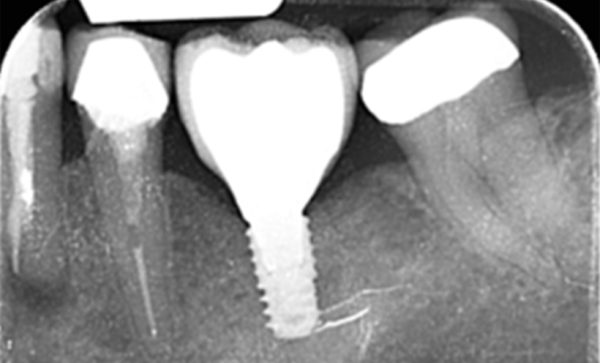

I have been a patient of Dr Verma for 8 years, my treatment has included crowns and an implant. Treatment plans and options are explained to me clearly, my concerns and anxieties are allieviated without hurry or pressure in a gentle and reassuring way. I feel my patient satisfaction is valued.

Sukal has been my dentist for many years, from simple check ups to a dental implant! I have always felt comfortable in the dentist chair and happily watched the TV on the ceiling while work is done on my teeth and never once felt any pain and always felt comfortable. I would never go anywhere else! Thank you all for being kind, caring and helpful at all times :-) Sarah Galloway